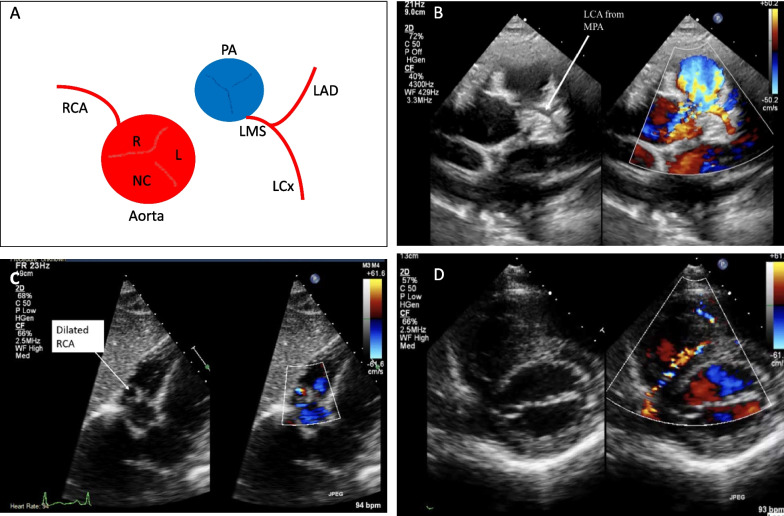

Transthoracic echocardiography is an essential and widely available diagnostic tool for assessing individuals reporting cardiovascular symptoms, monitoring those with established cardiac conditions and for preparticipation screening of athletes. While its use is well-defined in hospital and clinic settings, echocardiography is increasingly being utilised in the community, including in the rapidly expanding sub-speciality of sports cardiology. There is, however, a knowledge and practical gap in the challenging area of the assessment of coronary artery anomalies, which is an important cause of sudden cardiac death, often in asymptomatic athletic individuals. To address this, we present a step-by-step guide to facilitate the recognition and assessment of anomalous coronary arteries using transthoracic echocardiography at the bedside; whilst recognising the importance of performing dedicated cross-sectional imaging, specifically coronary computed tomography (CTCA) where clinically indicated on a case-by-case basis. This guide is intended to be useful for echocardiographers and physicians in their routine clinical practice whilst recognising that echocardiography remains a highly skill-dependent technique that relies on expertise at the bedside.